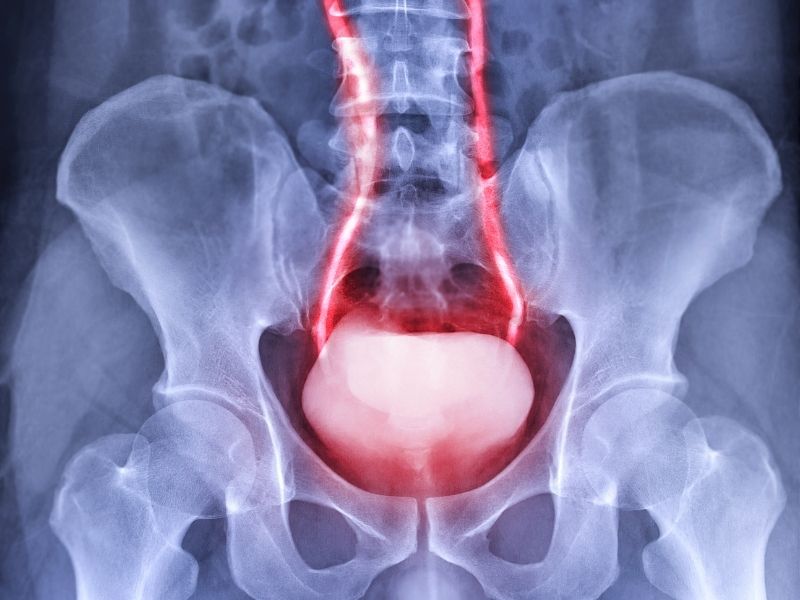

Prostat belirtileri, idrar yolunun mekanik olarak etkilenmesi veya prostat dokusunda gelişen iltihabi süreçler nedeniyle ortaya çıkabilir. Prostat bezinin idrar kanalını çevreleyen konumu nedeniyle, bezdeki hacim artışı ya da ödem idrarın geçişini zorlaştırabilir. Bu zorlanma bazen belirgin bir ağrı yapmadan, daha çok idrar akışında değişiklik ve işeme alışkanlıklarında farklılaşma şeklinde kendini gösterir. Şikayetlerin ilk fark edildiği dönem, çoğu kişide “idrarı eskisi kadar rahat yapamama” duygusudur.

Belirtiler genellikle iki grupta hissedilir: işeme sırasında yaşanan zorlanmalar ve işeme sonrasında devam eden rahatsızlıklar. İşeme sırasında ıkınma ihtiyacı, akışın zayıflaması, kesik kesik işeme veya başlamada gecikme görülebilir. İşeme sonrasında ise mesanede idrar kaldığı hissi, kısa süre sonra yeniden tuvalete gitme ihtiyacı veya damlama gibi yakınmalar öne çıkabilir. Bu bulgular tek başına bir tanı koydurmaz; prostat büyümesi, prostatit veya farklı bir idrar yolu problemi benzer belirtiler verebilir.